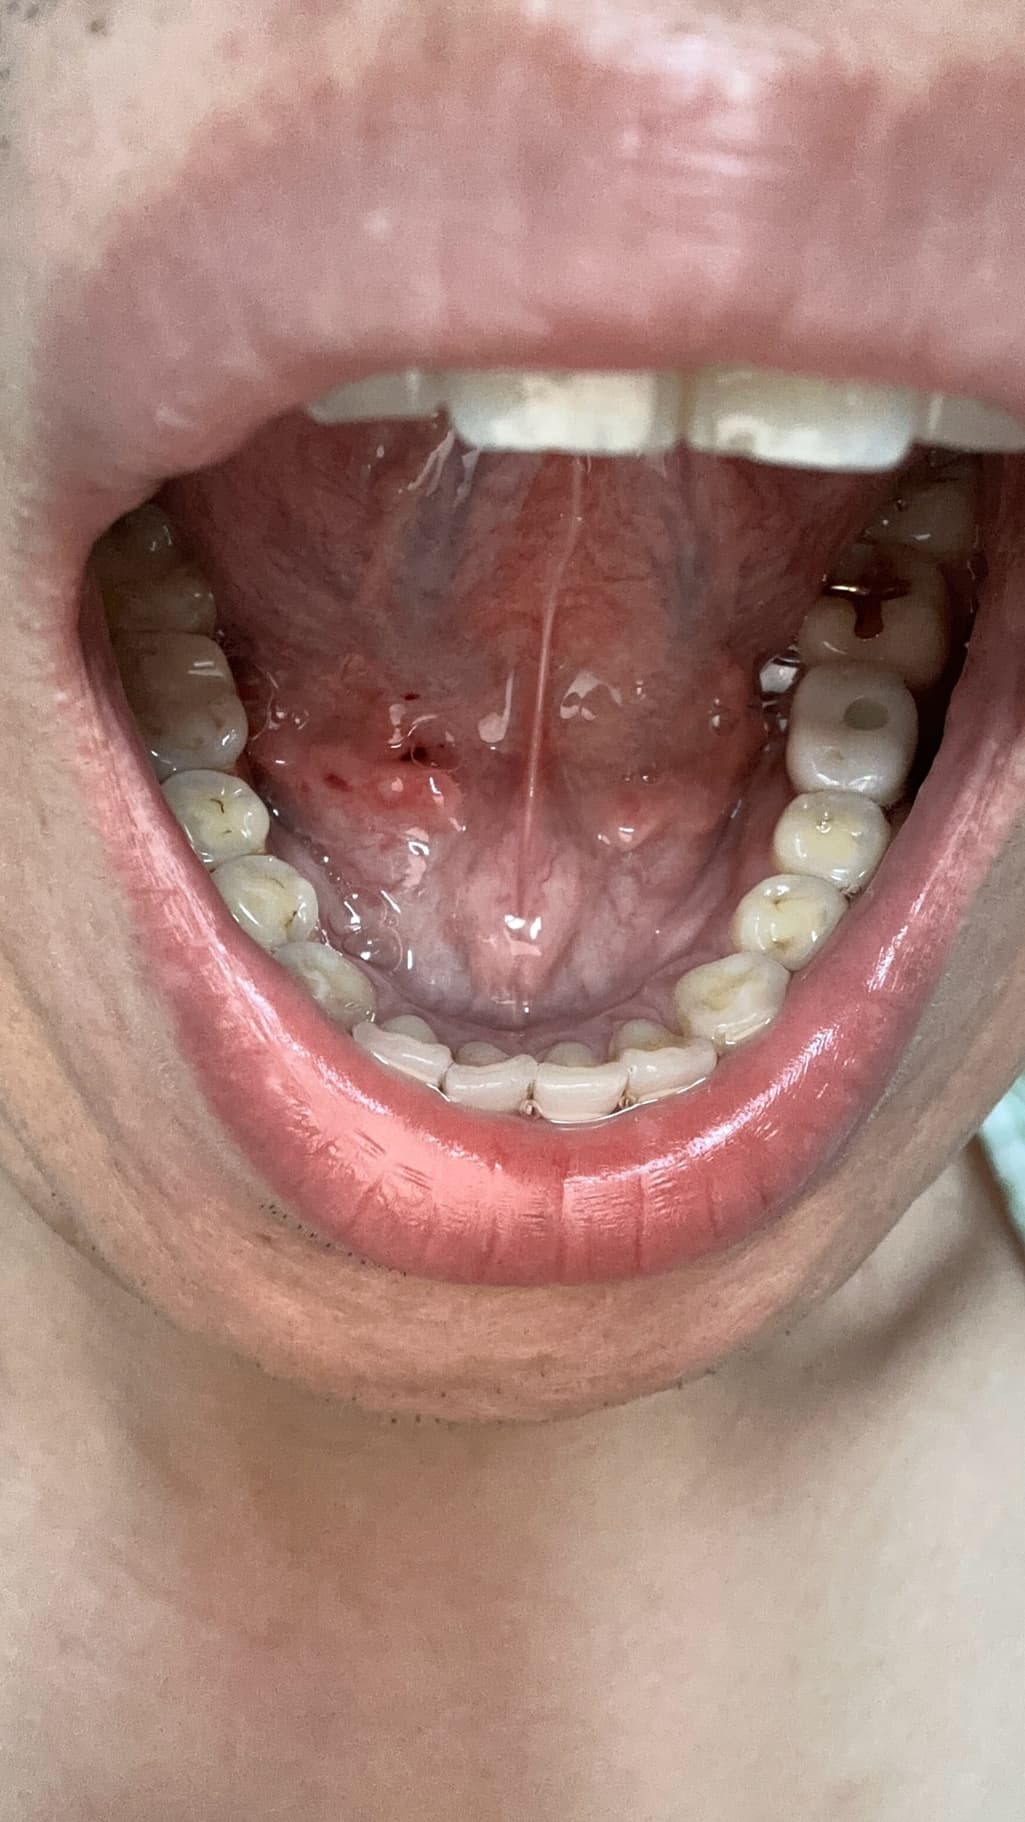

양치하다가 칫솔로 눌렀는데 피나는거처럼 됬어요

빨갛게 된부분이 있는것같고 그래서 이거 병원가봐야되는지 그냥 냅둬도 괜찮음지 궁금해요 어떻게하는게 좋을까요?? 병원은 무슨과인가요?

양치 중 칫솔로 인해 잇몸이 붉어지고 피가 나는 것은 잇몸 염증의 초기 증상일 수 있습니다. 칫솔질 시 잇몸에 과도한 힘이 가해지거나, 치석이나 치태가 쌓여 잇몸이 자극받았을 가능성이 있습니다. 우선 2~3일 정도는 부드러운 칫솔모를 사용하여 잇몸에 자극을 최소화하고, 치실이나 치간칫솔을 사용하여 꼼꼼하게 치아 사이를 청결하게 관리해주세요.

만약 며칠 후에도 증상이 호전되지 않거나, 붓기나 통증이 심해진다면 치과에 방문하여 정확한 진단을 받아보는 것이 좋습니다. 치과에서는 잇몸 상태를 확인하고 필요한 경우 스케일링이나 다른 치료를 통해 잇몸 건강을 회복할 수 있습니다.